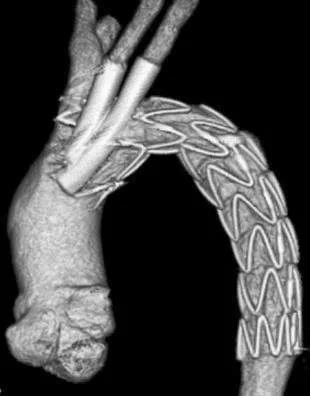

以往治疗该疾病的方法是开刀手术治疗,也就是开胸,将分层的主动脉置换成人工血管。但这种手术创伤巨大,风险大、并发症发生率高、围手术期死亡率高,令人望而生畏。近20年来,由于腔内治疗技术的不断发展和介入耗材的不断更新,部分夹层可以应用腔内治疗的办法来解决,也就是俗称的“放支架”,它利用主动脉内带膜的支架封堵夹层的破口(图二),从而达到治疗的目的。这种技术创伤小,仅仅需要在大腿根部切一个5cm长的小口就能解决问题,这种技术的出现让很多患者受益明显。

▲ 图二